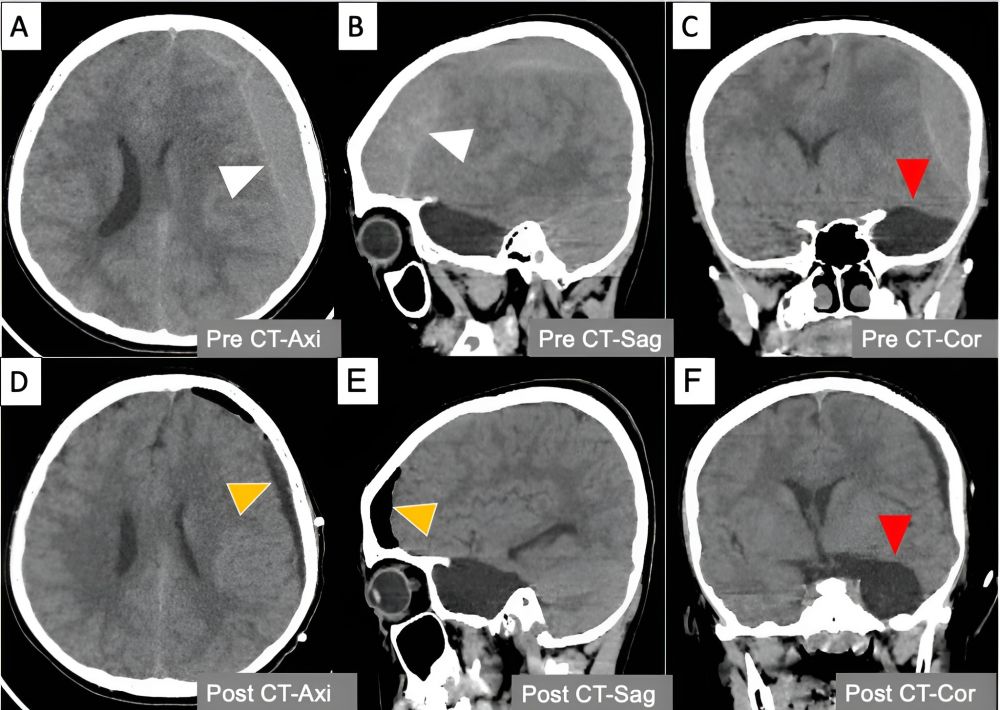

Hình 1. Máu tụ dưới màng cứng mạn tính xuất hiện đồng thời với nang màng nhện ở trẻ em

Hình 2. CT scan sọ não trước phẫu thuật - với máu tụ dưới màng cứng bán cầu não trái (đầu mũi tên trắng) và nang màng nhện thuỳ thái dương phải (đầu mũi tên đỏ), và CT scan sọ não sau phẫu thuật với máu tụ đã được lấy bỏ hoàn toàn (đầu mũi tên vàng)

Kết quả chụp CT lúc nhập viện lại cho thấy:

• Khối máu tụ dưới màng cứng mạn tính bên trái dày 17 mm, gây lệch đường giữa 12 mm và chèn ép não thất.

• Một nang màng nhện thái dương trái rõ ràng với kích thước 38 × 22 × 44 mm.

Bệnh nhi đã được chỉ định phẫu thuật dẫn lưu máu tụ qua lỗ khoan. Sau mổ, trẻ hồi phục nhanh chóng, hết đau đầu, nôn mửa và được xuất viện với tình trạng thần kinh hoàn toàn bình thường.